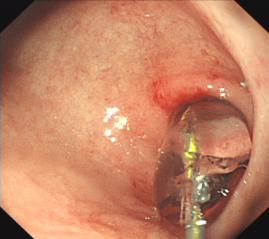

內(nèi)鏡下食管異物取出

胃底潰瘍并出血止血術(shù)